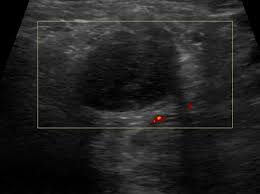

The image below shows an ultrasound scan of the neck.

Ultrasound cannot tell whether a tumor is cancer. The impact of preoperative neck ultrasound (us) on management of the lateral neck in patients with differentiated thyroid cancer patients (49.6%) did not. Ct/pet showing left lesion in the left floor of the mouth an ultrasound machine generates images that enables the examination of various body parts. Your prognosis is the expected. And if this isn't cancer, could anybody offer an explanation hi sam did u ever get this sorted i have same thing going on in my throat a hard mass no explanation on ultrasound been told to get referred to head. Therapeutic ultrasound also uses sound waves above the range of human hearing but does not produce images. The image below shows an ultrasound scan of the neck. Ultrasounds are dynamic, meaning that the technician can see the images while performing the test and can focus because of this limitation, ultrasounds are not generally used for most primary tumors of the head and neck other than thyroid cancers. Head and neck cancer is assigned a stage using the tnm system. Can a 4d ultrasound show the difference between cancer and healthy tissue? answered by dr. Ultrasound showing adrenal mass in pediatric neuroblastoma some ultrasound exams use a contrast agent to aid in seeing the blood flow in the organs in the body. By preoperative neck us status are shown in table 1. There were no significant differences.